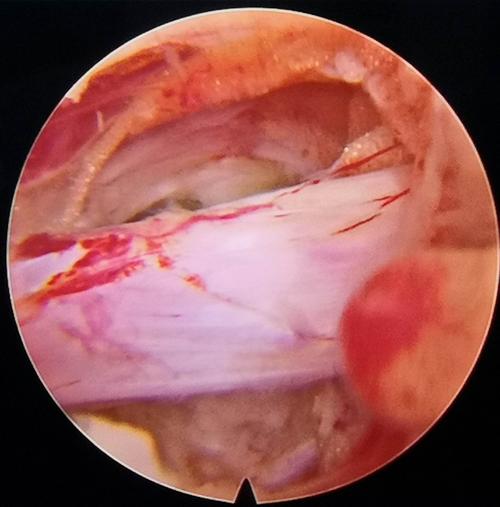

骨二科邓强主任团队杨镇源副主任医师完成甘肃省首例镜下纤维环缝合术

内窥镜辅助下腰椎髓核摘除术 纤维环缝合术

纤维环缝合术